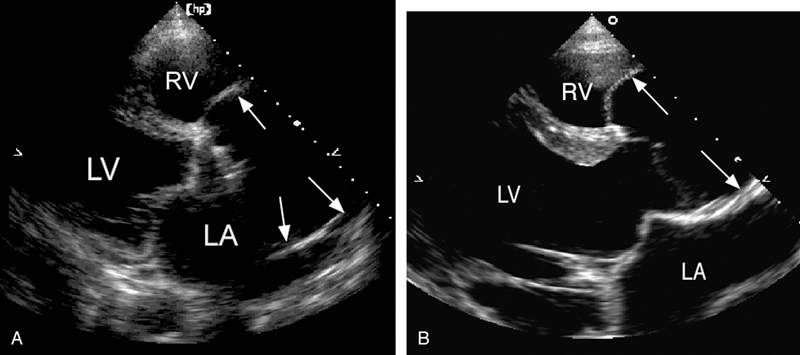

فحوصات تشخيصية لبعض امراض القلب والشرايين التاجية